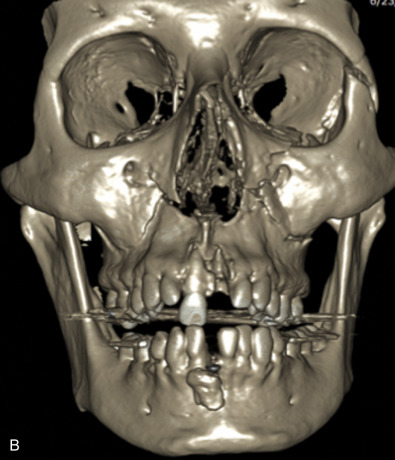

The gold standard for radiographic evaluation is thin-slice helical computed tomography (CT). Midface fractures are confirmed by axial, coronal, and sagittal views. The degree of comminution, bone loss, and detailed images of the fracture patterns can be assessed and juxtaposed to surrounding soft tissue structures. 3D reconstruction, when utilized, can aid in visualizing the complex 3D anatomical orientation of fracture fragments that occur in Le Fort injuries and facilitate reconstructive planning.

Le Fort III fractures generally consist of a combination of fractures that involve the palatine bones, the maxilla, the pterygoid plates, the nasal bones, lacrimal bone, and zygomas; they essentially separate the face along the base of the skull. The fracture pattern extends through the nasofrontal suture along the medial wall of the orbit, through the inferior orbital fissure and the lateral orbital wall to the zygomaticofrontal suture. In addition, the zygomaticotemporal suture is separated. The fracture extends across the sphenoid bone resulting in dysjunction at the pterygoid plates ( Figs. 1.13.16 and 1.13.17 ). The septum is separated from the cribriform plate of the ethmoid. Pure Le Fort III fractures are rare, and in actuality, most are ZMC fractures in conjunction with Le Fort I and II fractures lending the appearance of a comminuted “Le Fort III.” The force is delivered from the orbital level, resulting in craniofacial dysjunction. The fracture is generally more comminuted and more extensive on the side of force application.